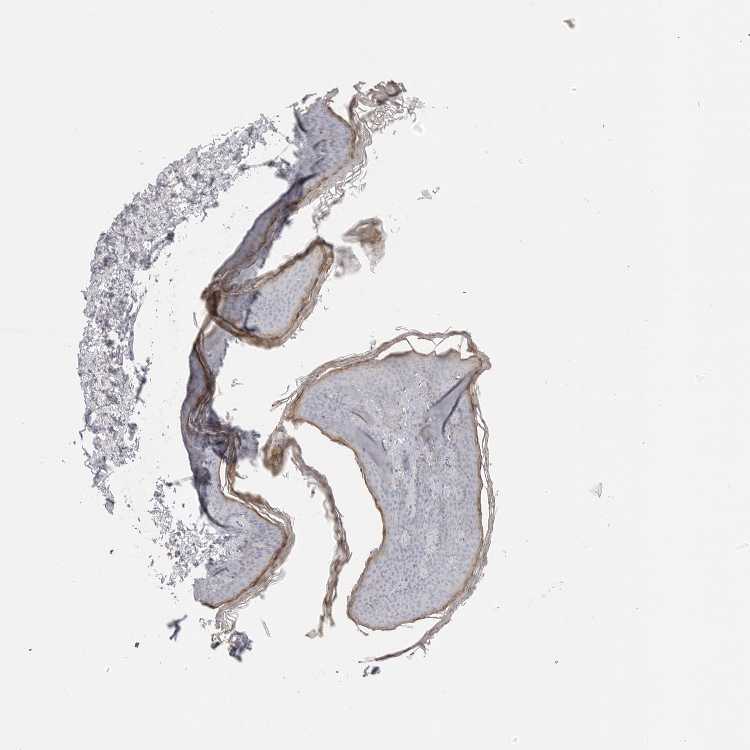

SKIN 1 - Antibody stainingi

Antibody staining in the annotated cell types in the current human tissue is reported as not detected, low, medium, or high, based on conventional immunohistochemistry profiling in selected tissues. This score is based on the combination of the staining intensity and fraction of stained cells.

Each image is clickable and will lead to virtual microscopy that enables deeper exploration of all samples and also displays staining intensity scores, fraction scores and subcellular localization as well as patient and tissue information for each sample.

Antibody HPA012853Antibody CAB026401

Langerhans Not detectedNot detected

Fibroblasts Not detectedNot detected

Keratinocytes Not detectedLow

Melanocytes Not detectedLow

SKIN 2 - Antibody stainingi

Epidermal cells Not detectedLow